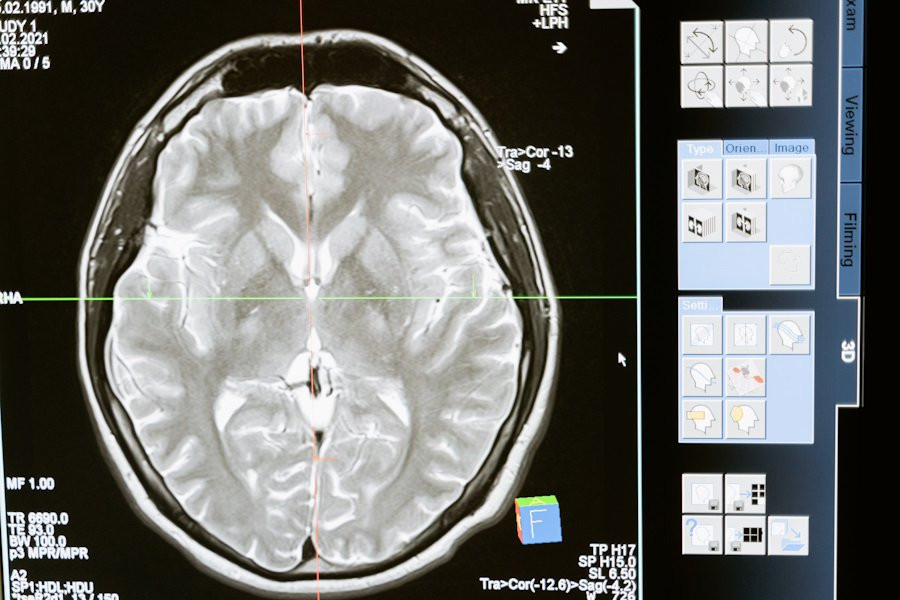

Исследователи из State University of New York сделали важное открытие, связанное с функцией молекулы KIBRA в деле консолидации памяти. Результаты их работы были опубликованы на портале Science Advances.

Ранее считалось, что память формируется исключительно за счет прочности связей между нейронами. Однако новое исследование показало, что белок KIBRA играет роль своеобразного «клея», который помогает поддерживать эти связи. Это открытие опрокидывает старую теорию и показывает, что KIBRA необходим для долгосрочного сохранения воспоминаний.

Ученые объясняют, что белок KIBRA взаимодействует с другими молекулами в мозге, чтобы предотвратить потерю воспоминаний. Несмотря на то, что KIBRA существует всего несколько дней, за это короткое время он успевает сыграть ключевую роль в поддержании нейронных связей.

Эксперименты на грызунах подтвердили, что KIBRA действительно важен для сохранения памяти. Этот белок не только участвует в формировании новых воспоминаний, но и является критическим элементом в механизме запоминания.

Понимание основных клеточных функций KIBRA может стать важным шагом на пути к лечению и профилактике нейродегенеративных заболеваний.